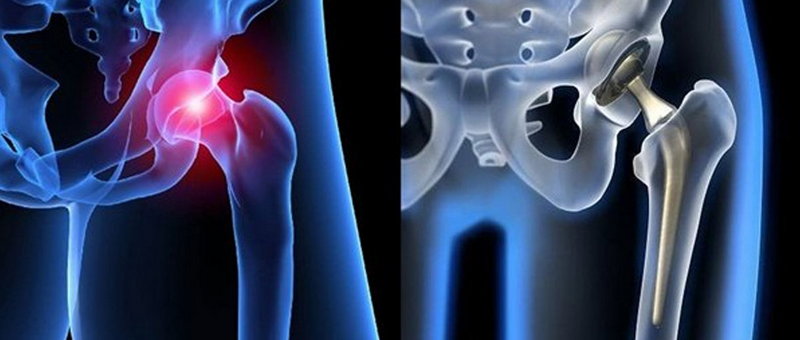

Эндопротезирование тазобедренного сустава: фото и схемы